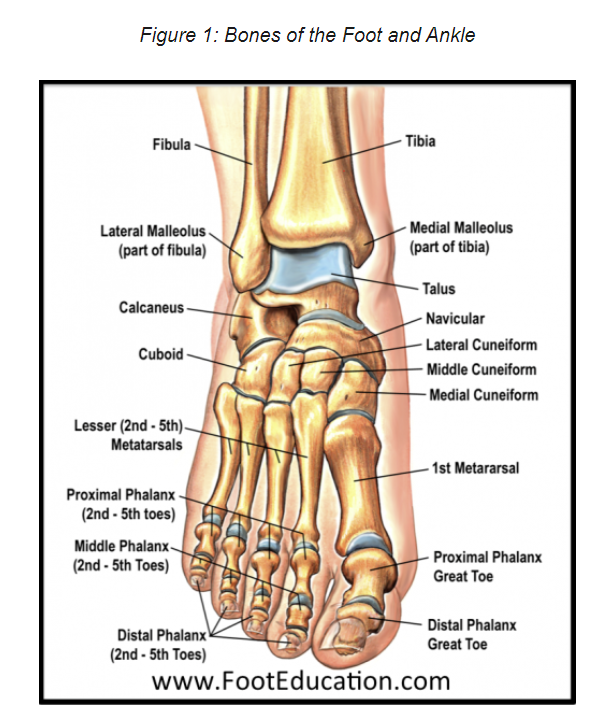

우리 몸 200여개의 뼈 중

발목에 26개씩 52개의 뼈가 존재함.

중족골 1,2,3 metatarsal bone - 발가락 기준으로 50%, 25%, 25%의 부하가 주어짐.

3개 cuneiform

1개 navicular

중족골 4,5 metatarsal bone - 발가락 기준으로 50% 50%의 부하가 주어짐.

1개 calcaneus

1개 cuboid bone